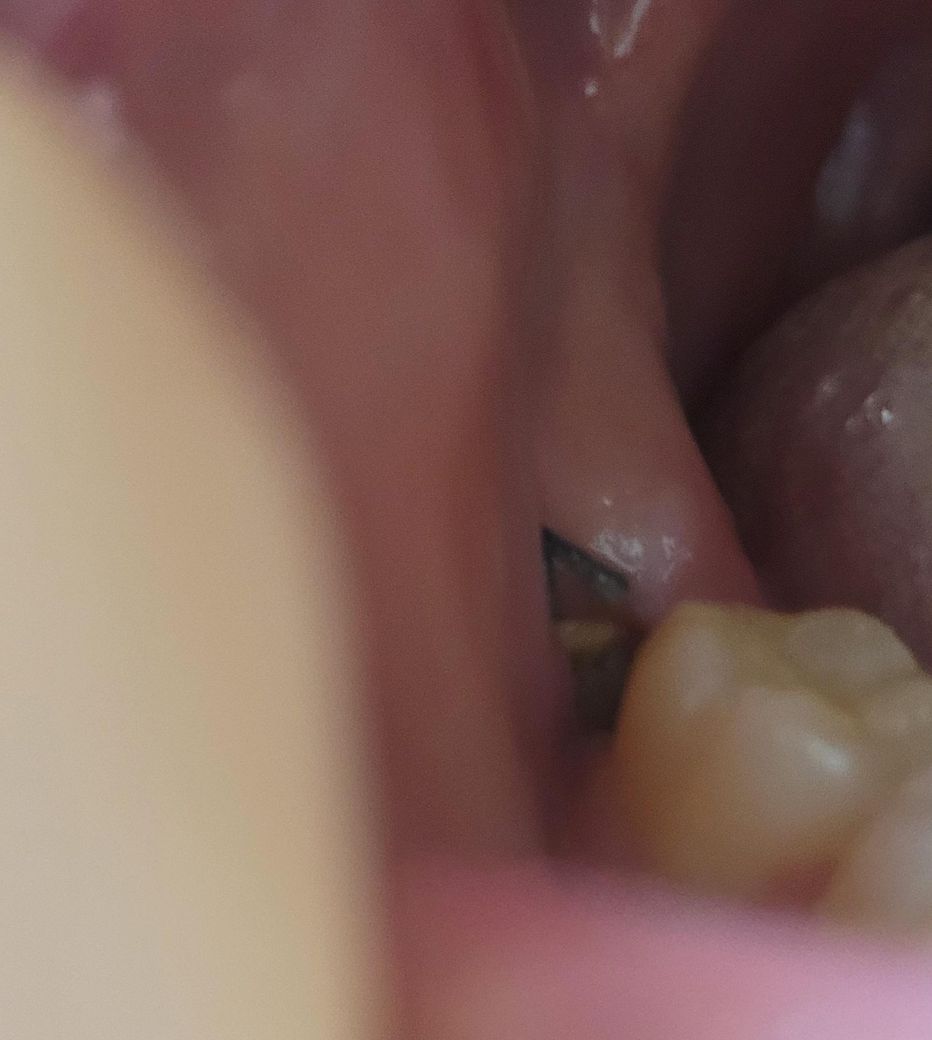

사랑니 발치한 지 7일차입니다. 발치한 구멍 안에 노란색 찌꺼기?와 하얀색 찌꺼기?들이 보이고 아무리 가글해도 빠지지 않습니다. 발치한 구멍쪽에서 비린맛? 쓴물?같은 것도 나옵니다

통증은 그리 크지 않고 약간의 이물감?과 붓기? 정도의 느낌만 있습니다. 저 구멍으로 계속 쓴물? 같은 맛이 나오고 발치한 구멍 안에 노란색 찌꺼끼? 같은것도 있는데 혹시 고름이나 염증일까요?? ㅠㅠ 설연휴라 치과도 갈수없어서 걱정됩니다 ..

• 1번 째 사진